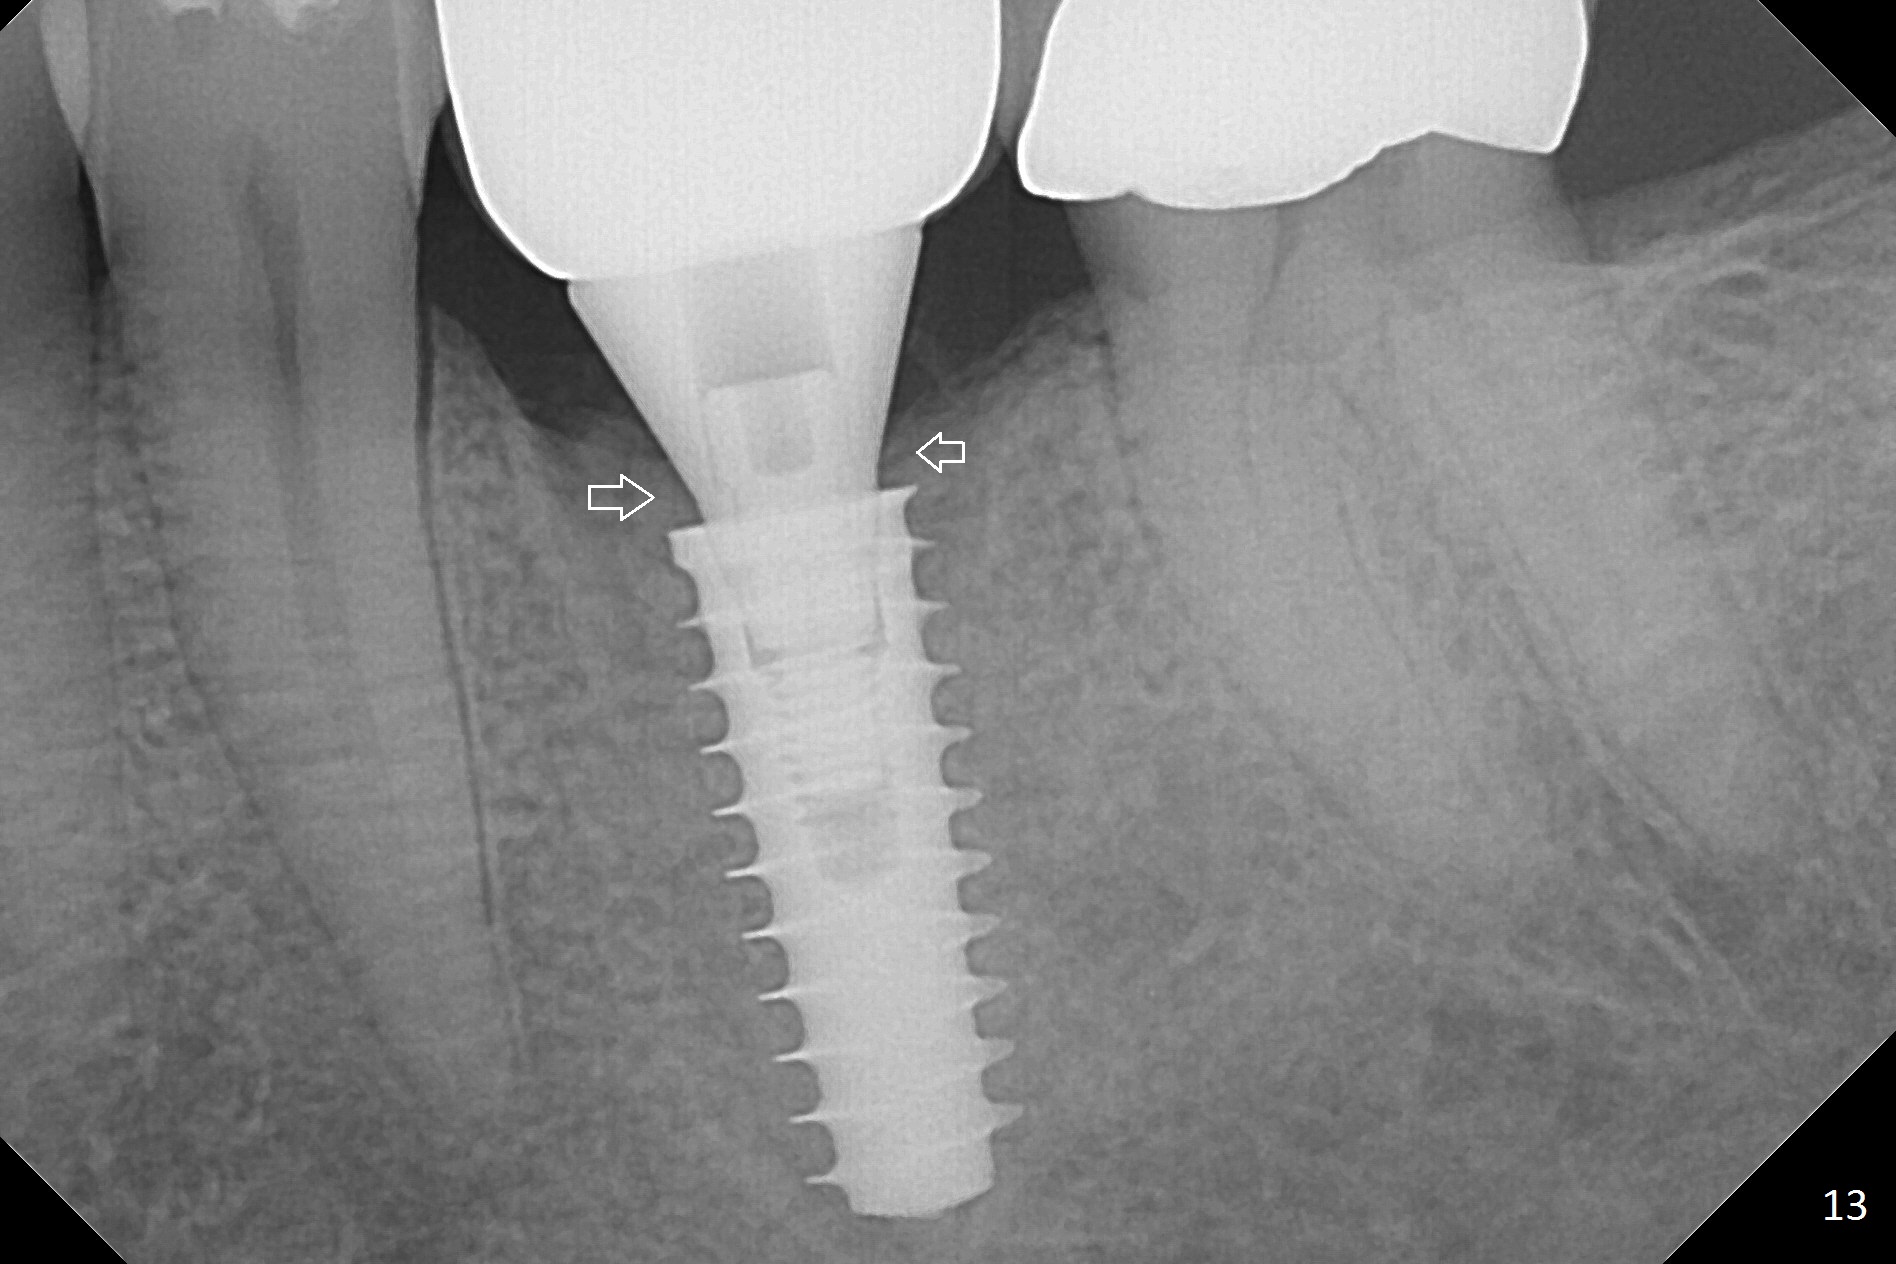

The gingiva looks healthy 8 months postop (3 months post cementation (after abutment screw retightening and addition of porcelain to proximal surfaces, Fig.12). New bone has apparently covered the implant plateau (Fig.13 arrows). Bone density between threads increases 9 months post cementation (Fig.14). There is 2 mm bone superior to the implant plateau mesial and distal 1 year 9 months post cementation (Fig.15,16). The crown/abutment is loose 3 times (3 months (Fig.14), 11 months (between Fig.14 and 15) and 2 years 3 months post cementation). In spite of being stable 3 years 10 months post cementation, a smaller abutment is placed (Fig.17 (PA), 18 (BW)) with impression for a new crown. After intraoral cementation, the new crown/abutment is removed for residual cement removal. When the complex is reseated, it is not smooth, probably due to proximal undercut. Fortunately the abutment appears to be completely seated, followed by 20 Ncm torque (Fig.19).